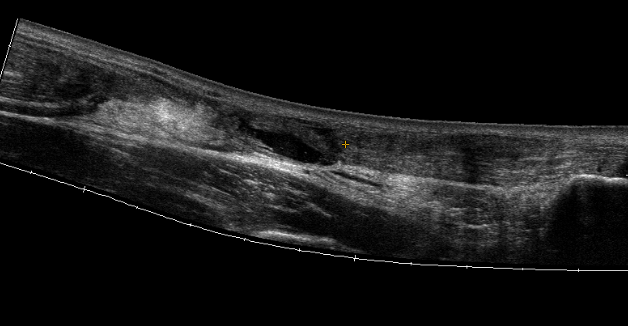

Ultrasound

Diagnose rupture and check reduction of tendon ends with plantarflexion

Aminlari et al J Emerg Med 2021

- systematic review

- ultrasound 95% sensitive and 99% specific for complete rupture